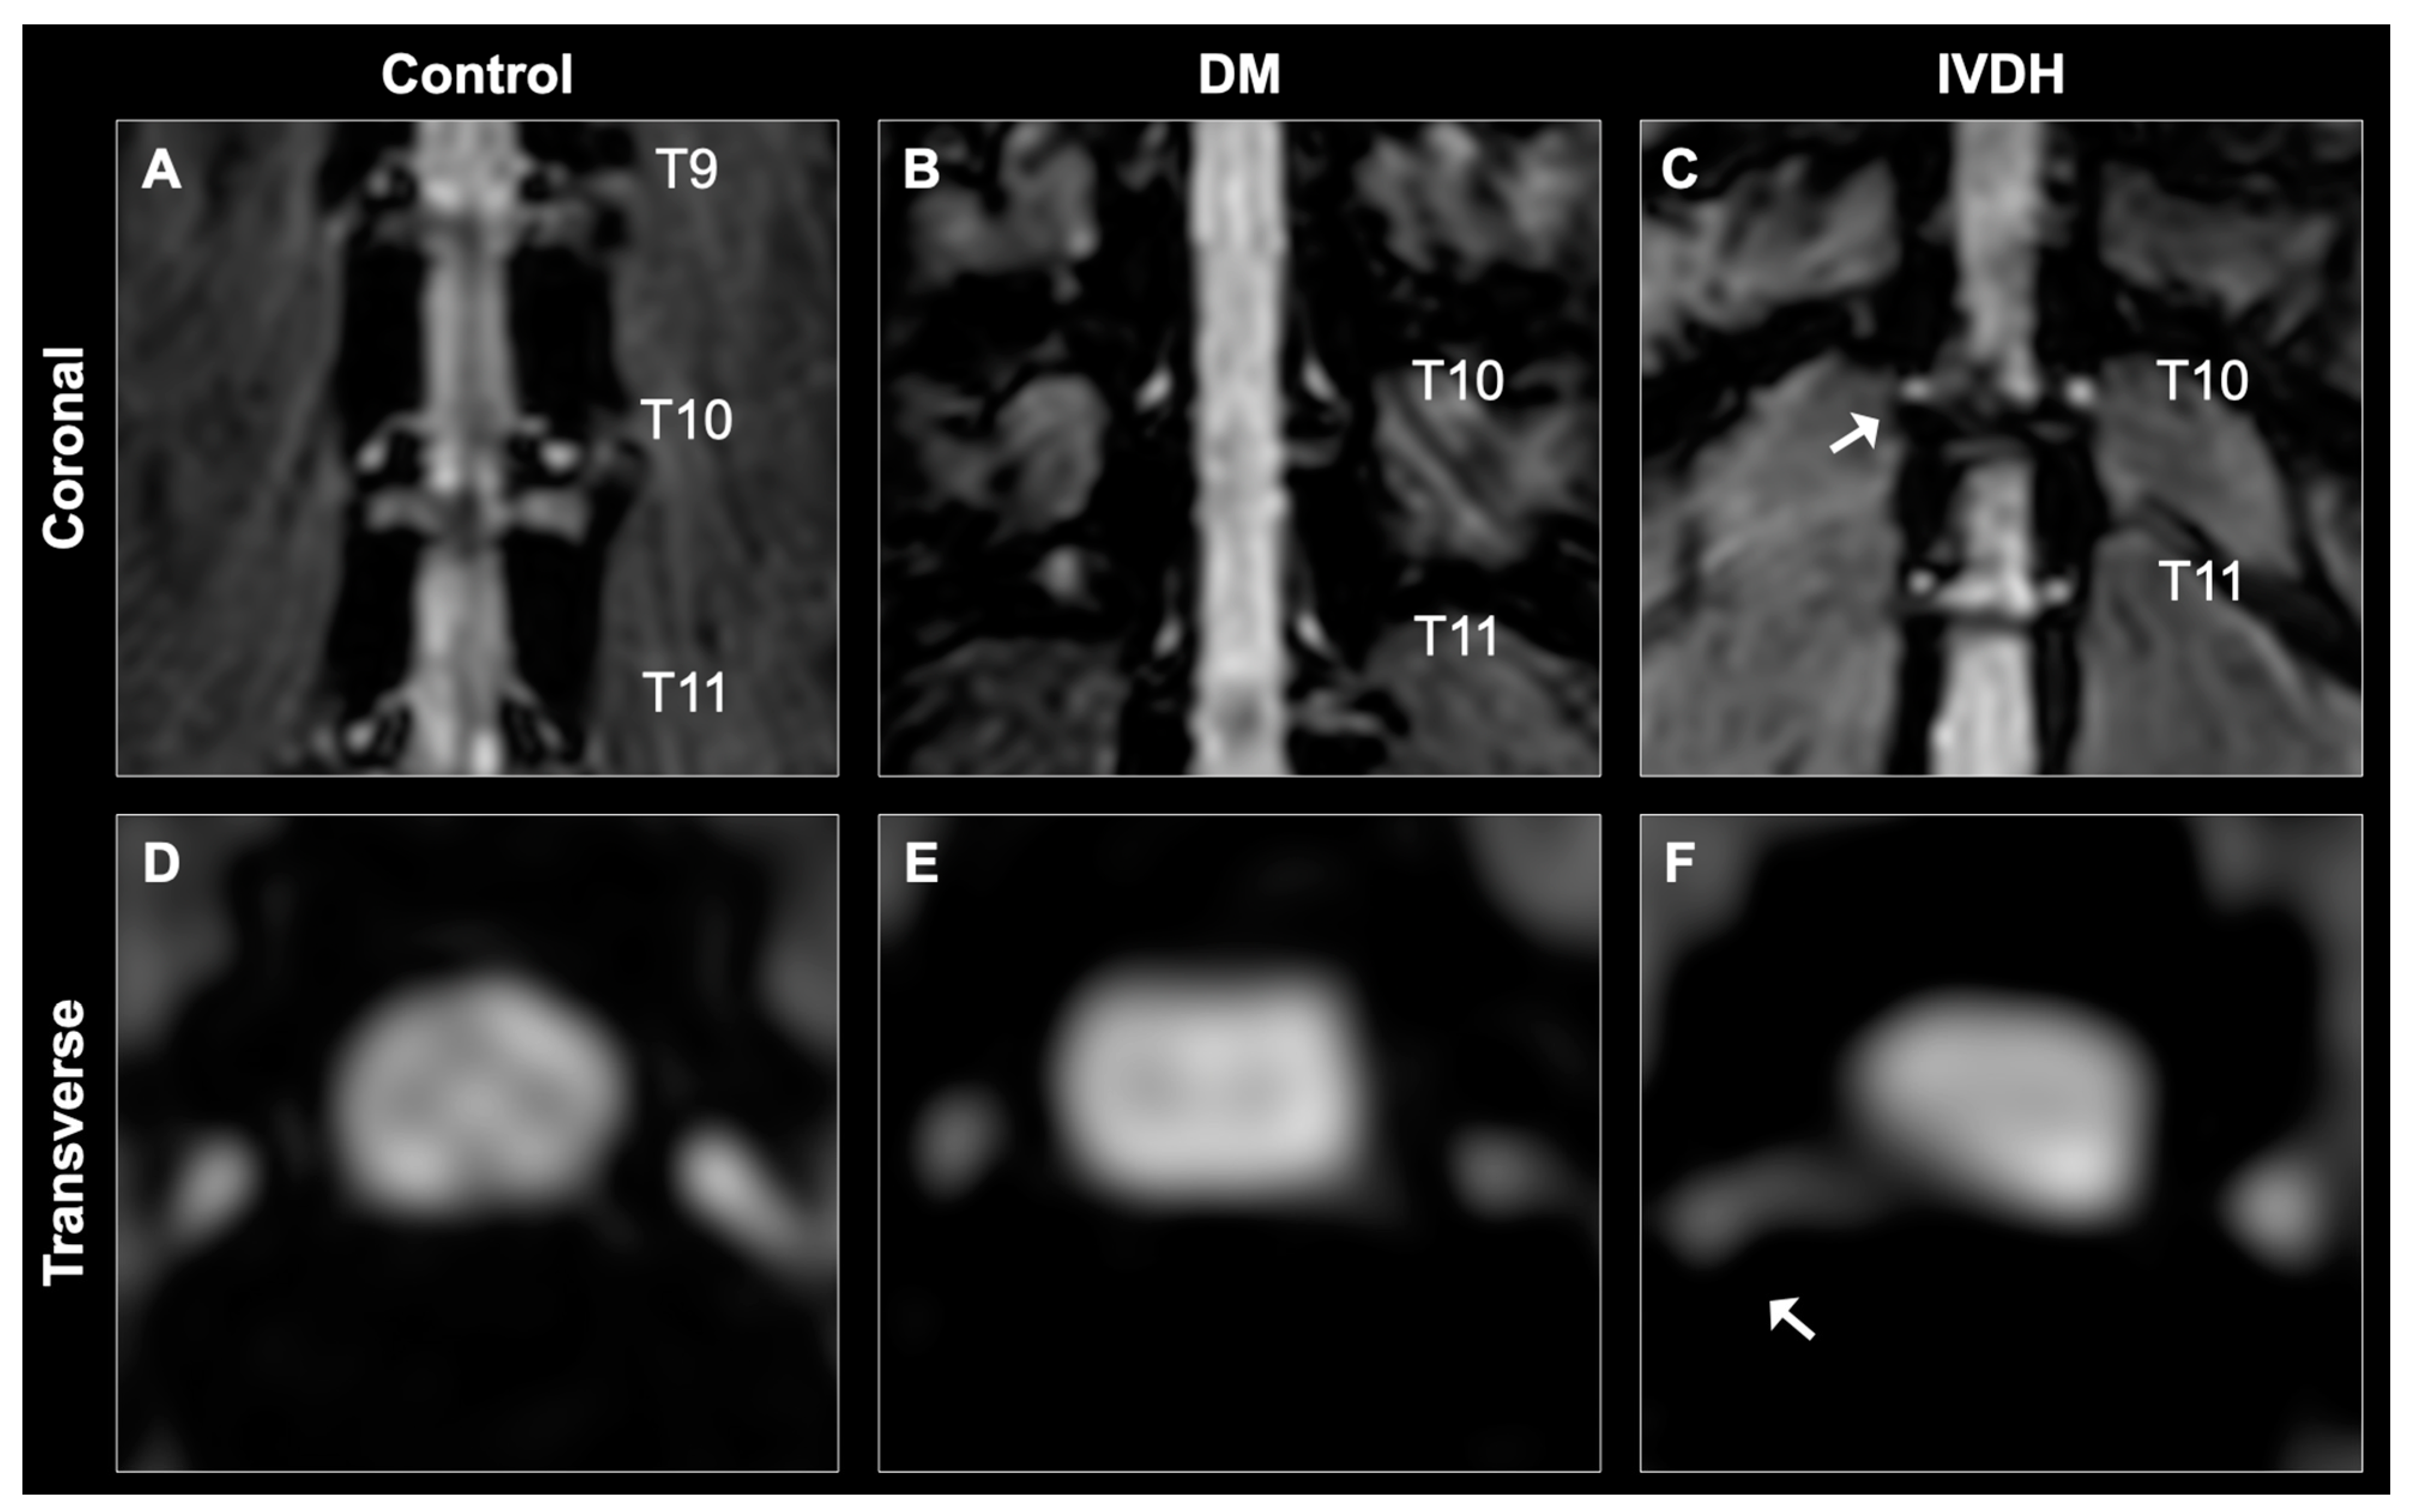

3.3. Normalized DRG Volumes between the DM, IVDH, and Control Groups